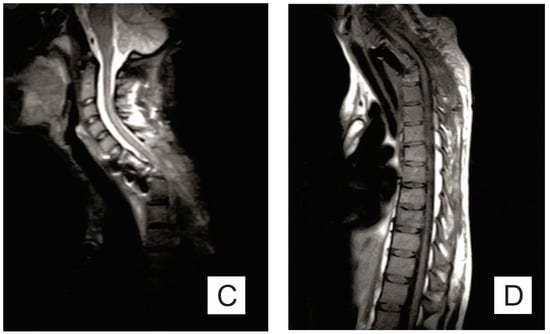

| Month I | C7 corpectomy and reconstruction with autologous graft from the iliac crest, macroscopic resection of the posterior arches C7-T1 and fixation with C4-C5-T3-T4 cervico-thoracic hybrid system |

| Month III | Ablation of osteosynthesis material and bone graft and T1 corpectomy, reconstruction with C6-T1 mesh fixed with proximal and distal screw |

| Month IX | Ablation of damaged osteosynthesis material mesh C6-T1, ablation of thoracic screws, and introduction of bilateral T3, T4, and T5 screws |